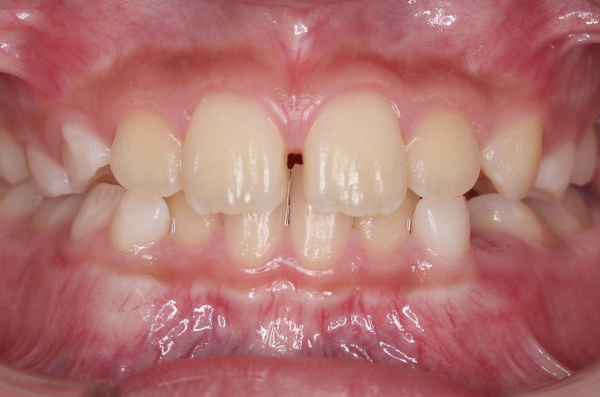

成長発育の口腔内変化

個々人でお口の中の成長発育は異なります。発育の変化の一例を掲載いたします。このように、永久歯に生え変わる前の写真があると、その後の成長発育の変化と比較ができます。

※画像クリックで拡大表示。